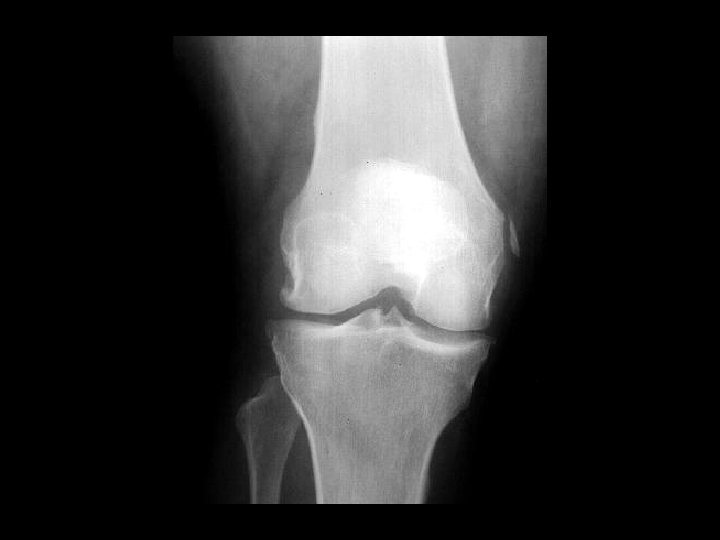

Pellegrini-Stieda disease • • Findings: – Linear ossific density adjacent to the medial femoral condyle Calcification or ossification of the MCL at its insertion site Sequela of previous injury NOT acute, usually not the site of pain